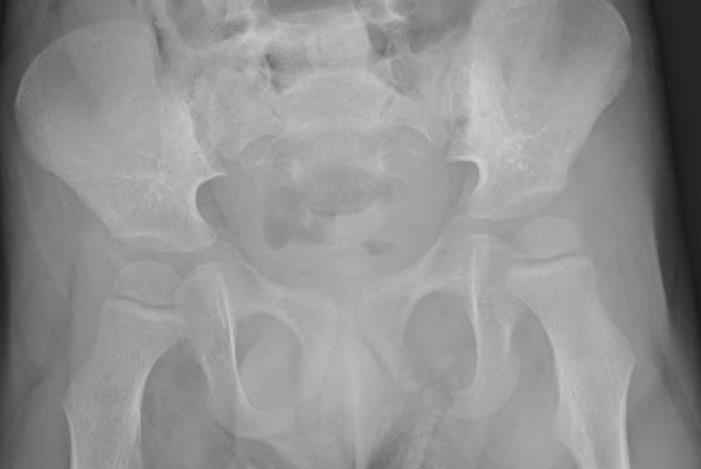

Hipdislocation

Regular follow-up, including pelvic Xrays from an early age, and early rehabilitative treatment are essential to prevent hip dislocation in children withseverecerebralpalsy.